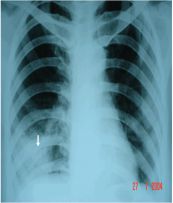

Hình ảnh áp xe phổi phải có mức nước mức hơi trên phim chụp x quang phổi thẳng được thể hiện như thế nào? Mời các bạn tham khảo bài viết dưới đây để hiểu rõ hơn nhé!